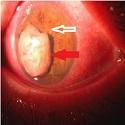

Carcinome vésical compliqué de métastase irienne

Rajae Derrar, Nourredine Boutimzine

PAMJ. 2014; 19: 232. Published 31 October 2014